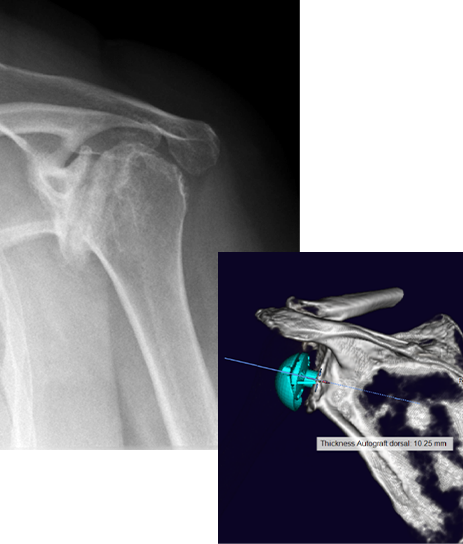

Pre-op

- 67-year-old female

- Severe pain

- Cuff tear athropathy

- Severe glenoid destruction

- Planned for bone allograft using mediCAD planning tool